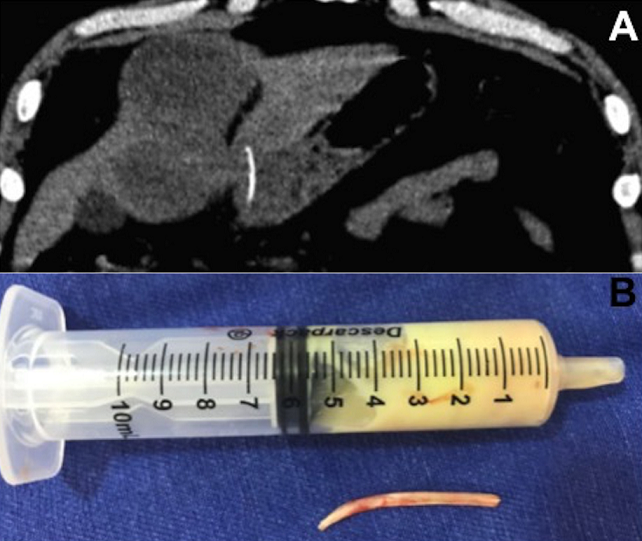

A 50-year-old previously healthy male presented with epigastric pain for 10 days and fever in the last three days. Laboratory testing was remarkable for elevated white blood cells at 19,580/mm3 and C-reactive protein of 83.9 mg/dl. Abdomen computed tomography showed a small linear structure with calcium density, transfixing the wall of the gastric antrum and penetrating the left hepatic lobe; an oval massive hypodensity was observed in the surrounding liver parenchyma (A); pneumoperitoneum, free intra-abdominal fluid or vesicular changes were not observed. The hypothesis of gastric perforation due to ingestion of a foreign body with abscess formation was raised. In a new clinical interview, the patient reported a routine habit of fish consumption. Abdominal surgical approach was performed which confirmed the presence of a fish bone and the hepatic collection with purulent fluid (B). After seven days of surgery and treatment with intravenous ceftriaxone and metronidazole, the patient evolved with clinical and laboratory improvement and was discharged. Gastrointestinal perforation by an ingested fish bone resulting in hepatic abscess is very rare. In these cases, the site of perforation is usually in the stomach or duodenum with the abscess most commonly developing in the left hepatic lobe. The classic indicators of hepatic abscess, such as fever with chills, abdominal pain and jaundice are present in only a small number of patients. Among several causative objects that can perforate the gastrointestinal tract are included toothpicks, sewing needles, hairpins, wire, fish bones, chicken bones and dental plates.